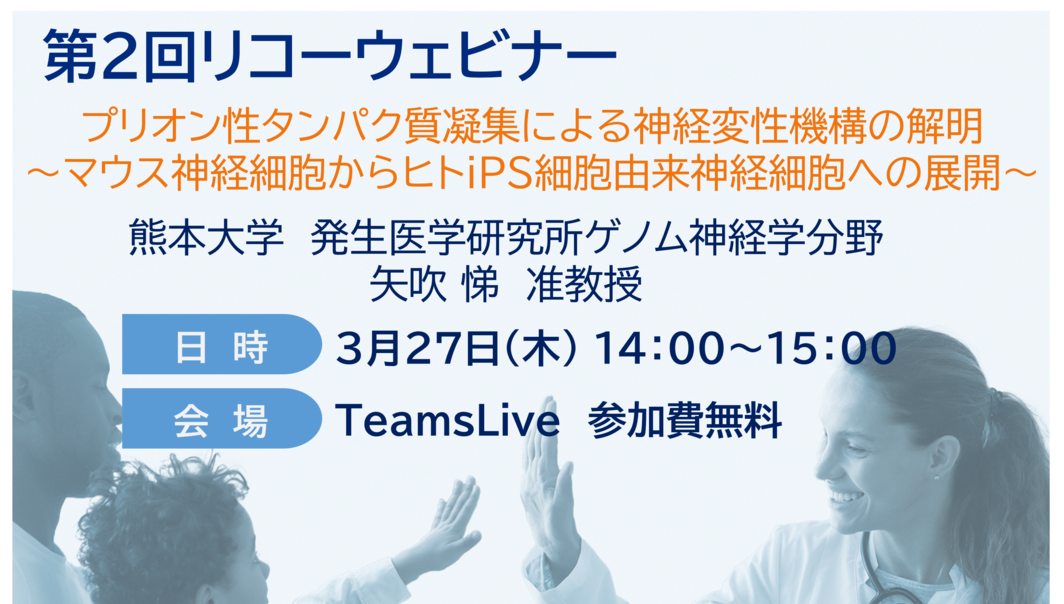

第2回 リコーウェビナー「プリオン性タンパク質凝集による神経変性機構の解明」熊本大学 矢吹 悌 准教授 2025年3月27日(木)14:00~15:00